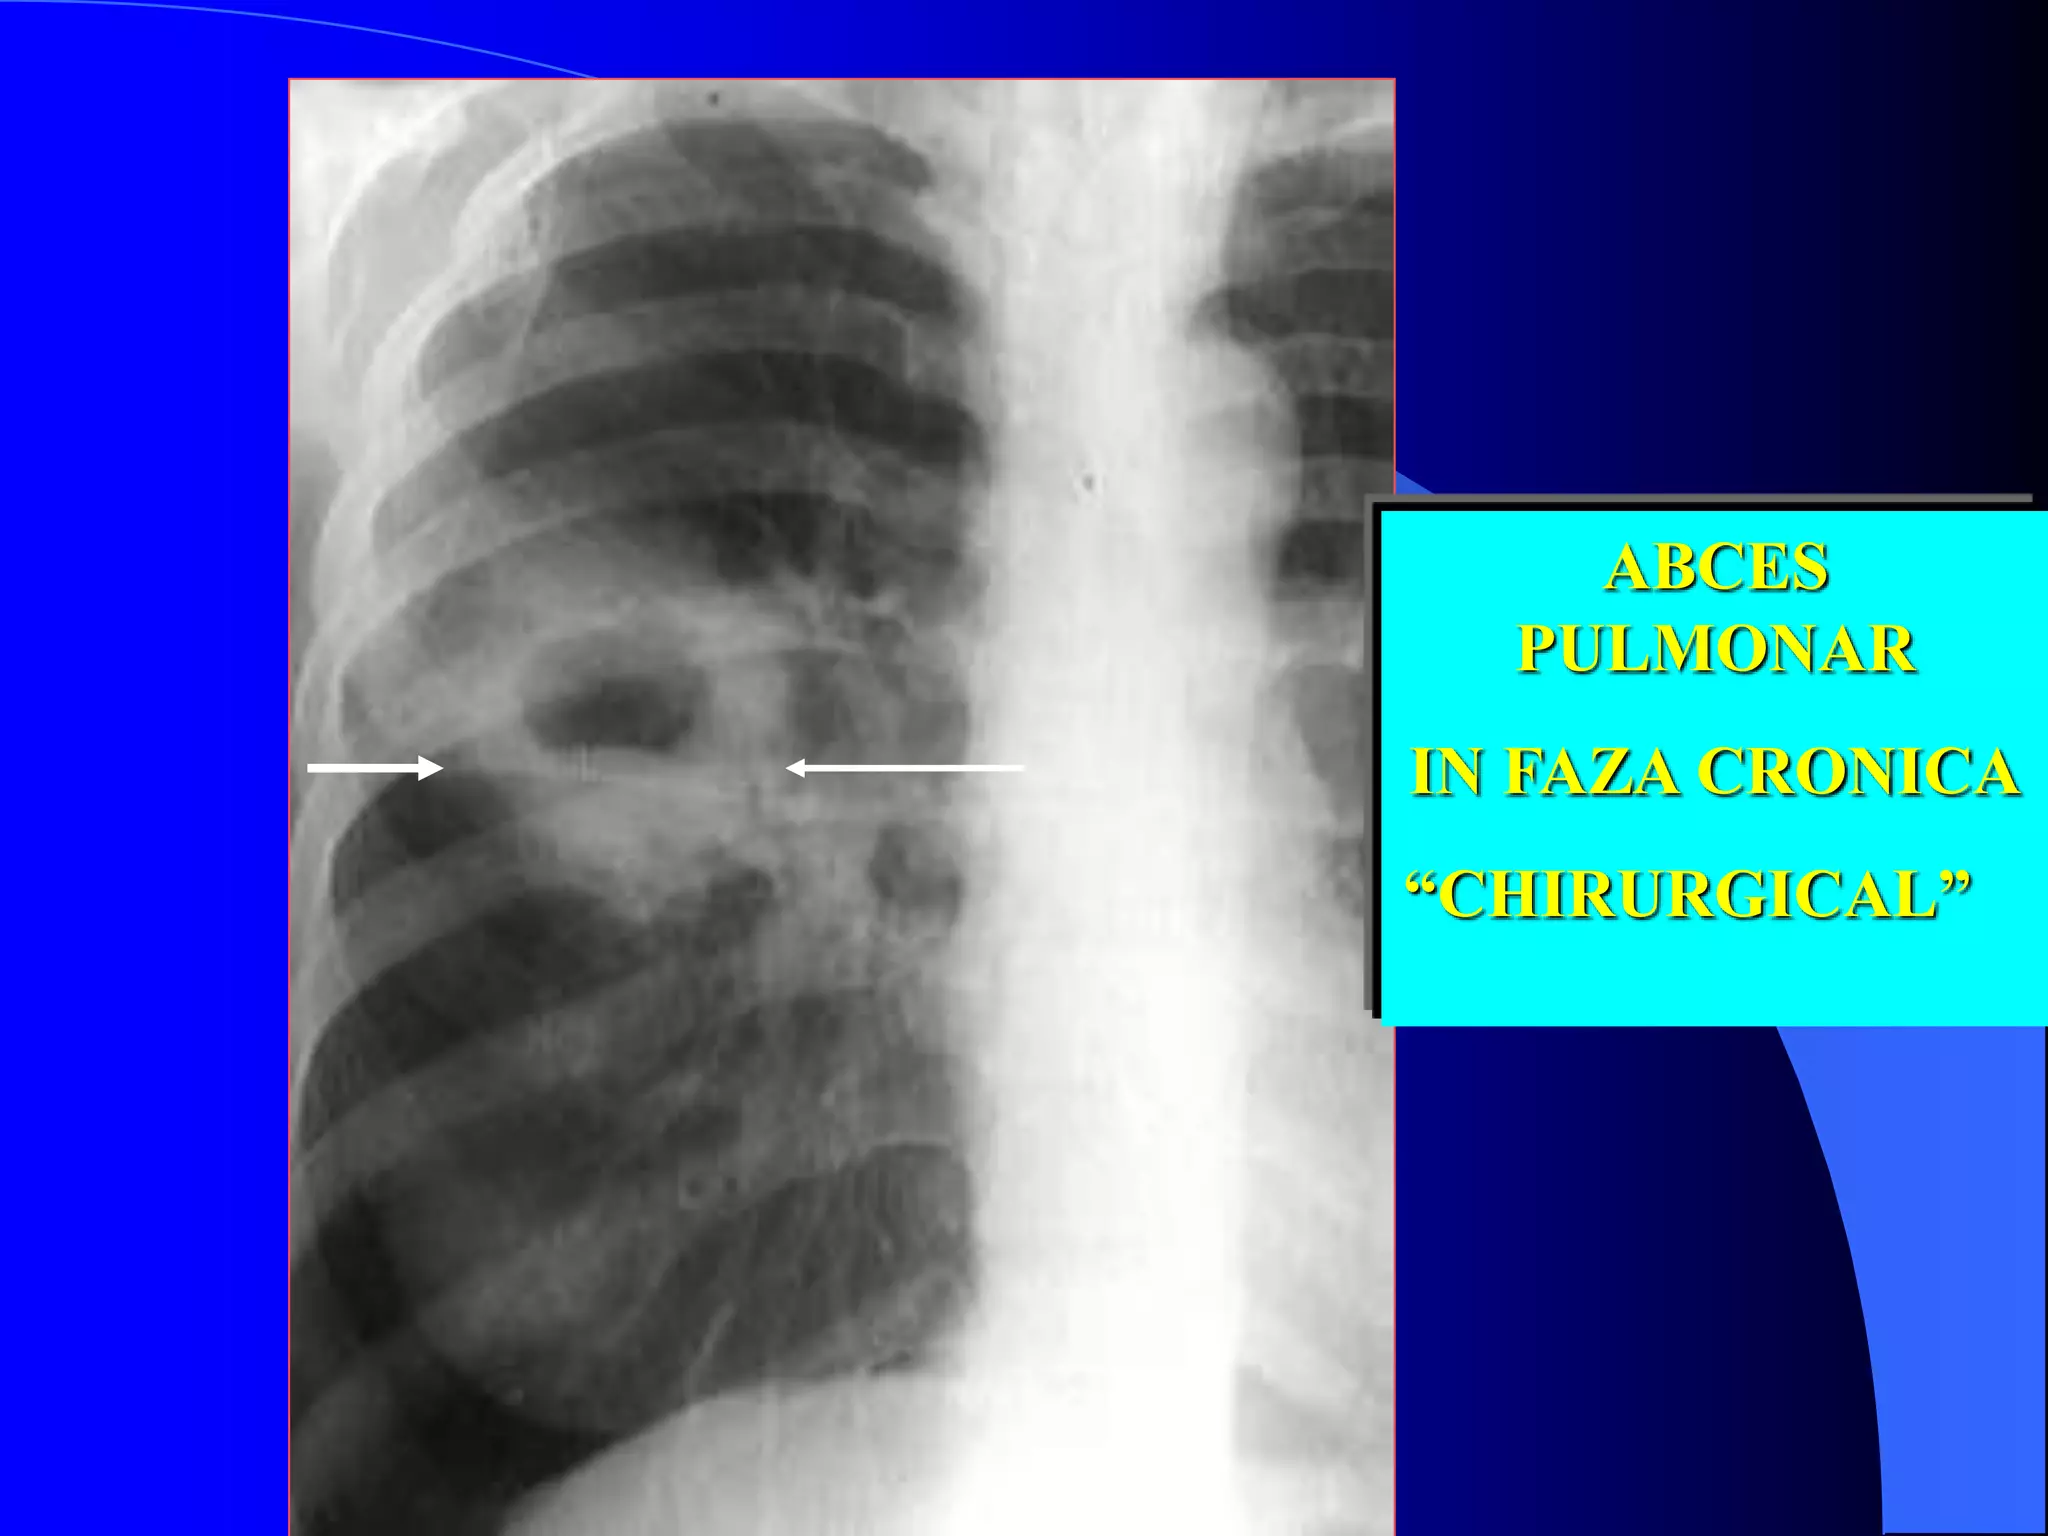

în interiorul ariei de condensare pulmonară se observă două imagini hidro-

aerice suprapuse (aspect în gură de cuptor)

ABCES

PULMONAR

IN FAZA CRONICA

“CHIRURGICAL”